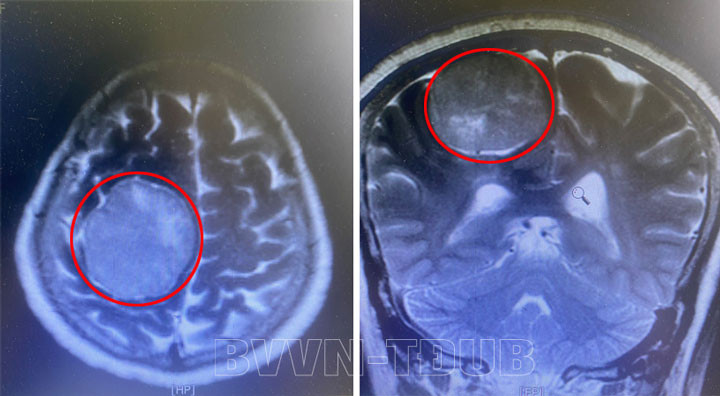

Người bệnh là D. T. C. 66 tuổi (trú tại Trưng Vương – Uông Bí), người bệnh có tiền sử tăng huyết áp. Khoảng 3 ngày trước khi nhập viện, người bệnh có biểu hiện yếu nửa người trái. Trên hình ảnh chụp cắt lớp vi tính sọ não phát hiện khối u não vùng đỉnh phải kích thước 4,7x5,6cm.

| Khối u não khổng lồ trên phim chụp |